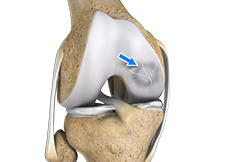

Anterior Cruciate Ligament (ACL) Tear

The anterior cruciate ligament, or ACL, is one of the major ligaments of the knee that is in the middle of the knee and runs from the femur (thighbone) to the tibia (shinbone). It prevents the tibia from sliding out in front of the femur. Together with posterior cruciate ligament (PCL) it provides rotational stability to the knee.

ACL Reconstruction

The anterior cruciate ligament is one of the major stabilizing ligaments in the knee. It is a strong rope like structure located in the centre of the knee running from the femur to the tibia.